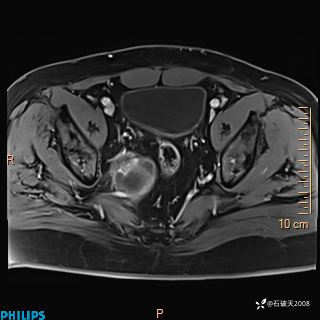

2023年3月份MRI影像

增强轴位